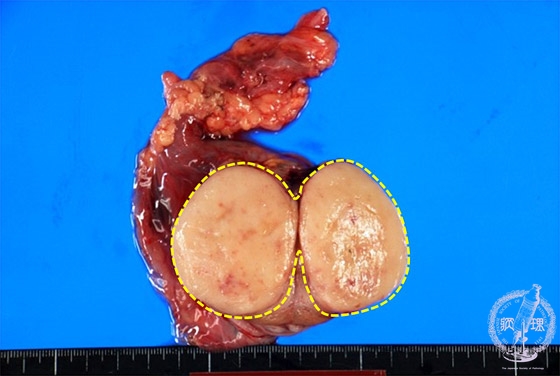

- ★(4)Seminoma (Germ cell tumor)

Macroscopic appearance: Seminoma. Soft and well marginated pale to yellow tumor with bulging cut surface (yellow dotted line). Unless other types of germ cell tumors coexist, hemorrhage or necrosis is rarely found.